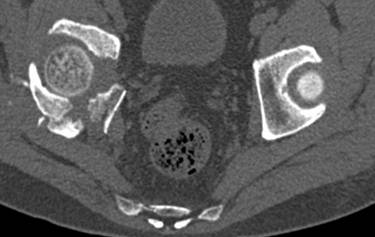

[Ortho] перелом правой половины таза

высылаю дополнительно  сканы.